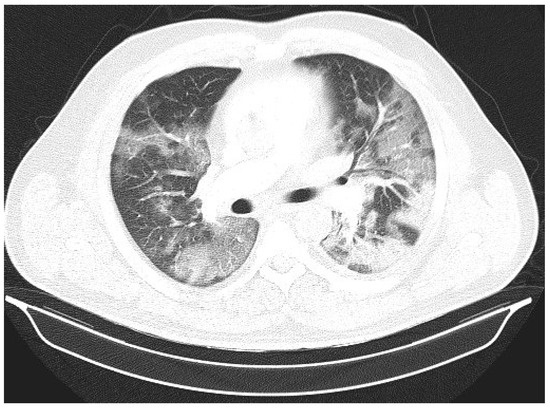

Laboratory findings were mostly normal; C-reactive protein was elevated in all patients with a mean value of 129.7 ± 80.74 mg/L. The arterial blood gas analysis showed hypoxemic respiratory failure. Chest X-rays in all patients showed bilateral inhomogeneous infiltrates (Figure 1 and Figure 2). In three patients, CTPA was performed, which ruled out pulmonary thromboembolism, but ground-glass opacifications with consolidation of the lung parenchyma were described in all of them (Figure 3 and Figure 4) [15].

Figure 1. Chest X-ray upon admittance: patient 5. Bilateral inhomogenous infiltrates typical for COVID-19 pneumonia (the “L” orientation marker indicates the left side).